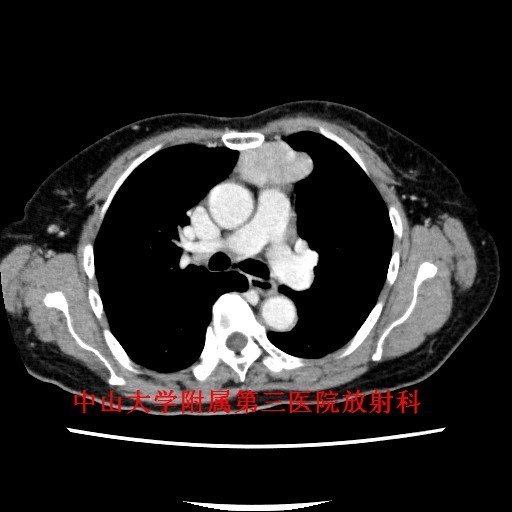

主诉:咳嗽咳痰1月余,发现前纵隔肿物4天。 病史:老年女性,慢性病程。患者于1月余前出现反复咳嗽,咳痰,无痰中带血及咯血,遂至我院门诊就诊,行胸片及胸部CT检查提示“前纵隔肿物,胸腺瘤?”。

查体:胸廓对称无畸形,无挤压痛,呼吸运动度及语颤对称,双肺叩诊清音,呼吸音清晰。 辅查:胸部CT示:前纵隔肿物,胸腺瘤?

讨论:胸腺瘤是前纵隔最常见的肿瘤,约占成人前纵隔肿瘤的50%。目前,CT是公认的早期检出及诊断胸腺瘤的最佳方法。CT一般表现为:圆形、卵圆形或分叶状肿块,边界清晰,多数密度均匀,可见钙化;大部分肿瘤生长不对称,居于前纵隔的一侧;直径<2cm的胸腺瘤可仅表现为正常胸腺边缘局部隆起;增强扫描仅有轻度强化。主要应与胸腺增生鉴别,后者胸腺体积弥漫性增大,以左右两叶增厚为主要特征,但仍保持正常形态,而胸腺瘤为局部结节。 参考文献:杨蕊梦,许乙凯,冯婕等.胸腺瘤的MSCT-病理-临床综合诊断[J].放射学实践,2007,22(7):711-713.